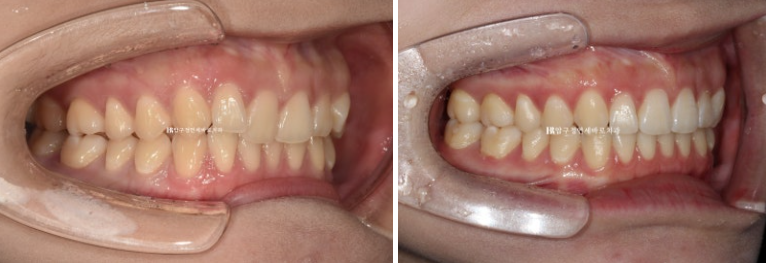

24.02~24.11

문제의 우측 II급 교합관계가 거의 I급으로 좋아졌습니다.

고무줄을 열심히 껴준 덕입니다.

좌측교합은 원래 I급이고 위아래 어금니 교합이 좀 더 긴밀해졌습니다.

뒤로 쓰러져 있던 앞니가 나오면서 악궁모양이 네모진 형태에서 원형으로 바뀌었습니다.

아래 악궁모양이 좋아졌습니다.

중심선도 여전히 1mm 정도 차이가 나지만 처음에 비해 개선되었습니다.

옥니와 덧니가 해결이 되니 미소가 훨씬 깔끔하고 환해보입니다.